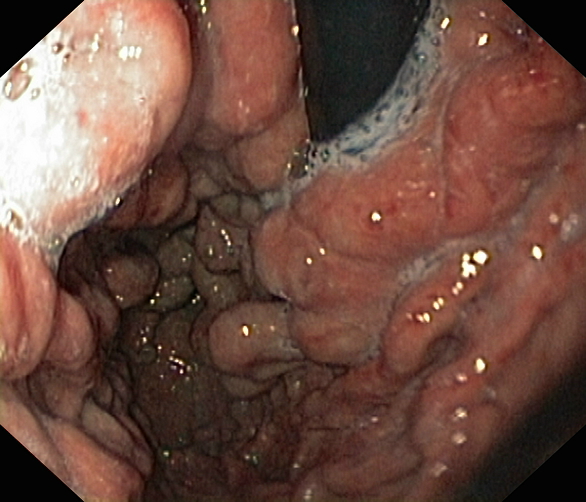

Krstic, Miodrag